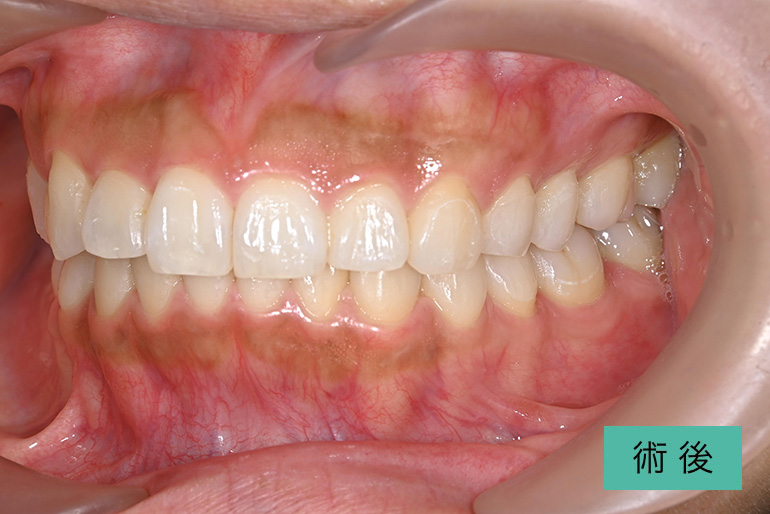

オールセラミック②

| 治療内容 | 上顎前歯右上3番から左上3番のセラミック冠 |

| 治療期間・回数 | 約1ヶ月、3回 |

| 費用(税込) | ¥990,000(165,000/1本)(補綴費用) ※自由診療 |

| リスク・副作用 | 疼痛、補綴物の脱落、咬合違和感、破折 |